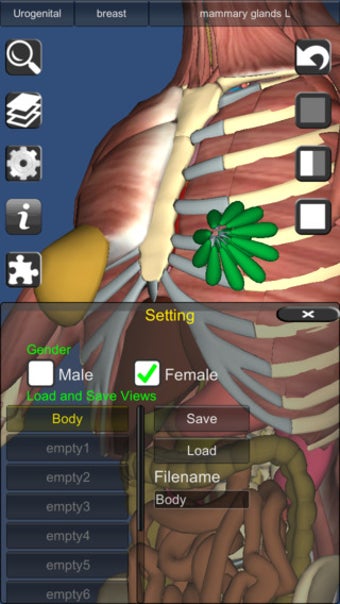

يشبه 3D Anatomy Lite سلسلة Essential Anatomy من التطبيقات من حيث أنه يوفر ميزة ممتازة أداة ثلاثية الأبعاد للمعلمين والطلاب وعشاق الطب العام من أجل استكشاف جسم الإنسان strong>.

على الرغم من أنها لا تبدو رائعة مثل Essential Anatomy ، إلا أنها مفصلة مع القدرة على اعرض النص من أي زاوية strong> بالرغم من أنه يتعين عليك الترقية إلى الإصدار الكامل لمشاهدة كل شيء. p> هناك أيضًا اختبارات ثلاثية الأبعاد strong> لاختبار تكوين معرفتك 3D Anatomy Lite مصدر ممتاز للطلاب. p>